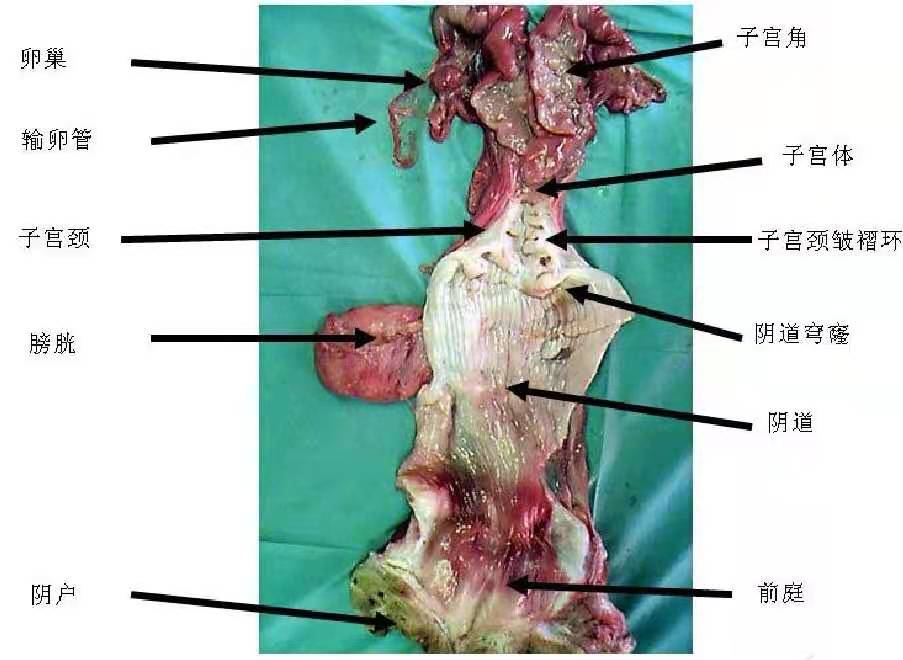

任务2 母畜生殖器官概述.文档

2.母畜生殖器官.docx